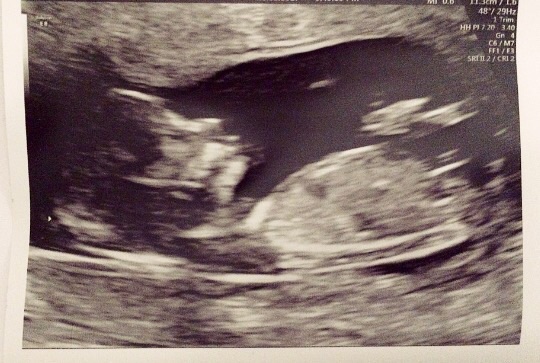

This is my 13 week scan taken today.

Does anyone have an idea as to what gender it could be please?

This is my first baby.

Tricky one, I think I see stacking, slight boy lean for me, what you hoping for? X

Boy lean from me

Stacking means the nub looks like it is raised=boy. Long, forked, flat nubs=girl.